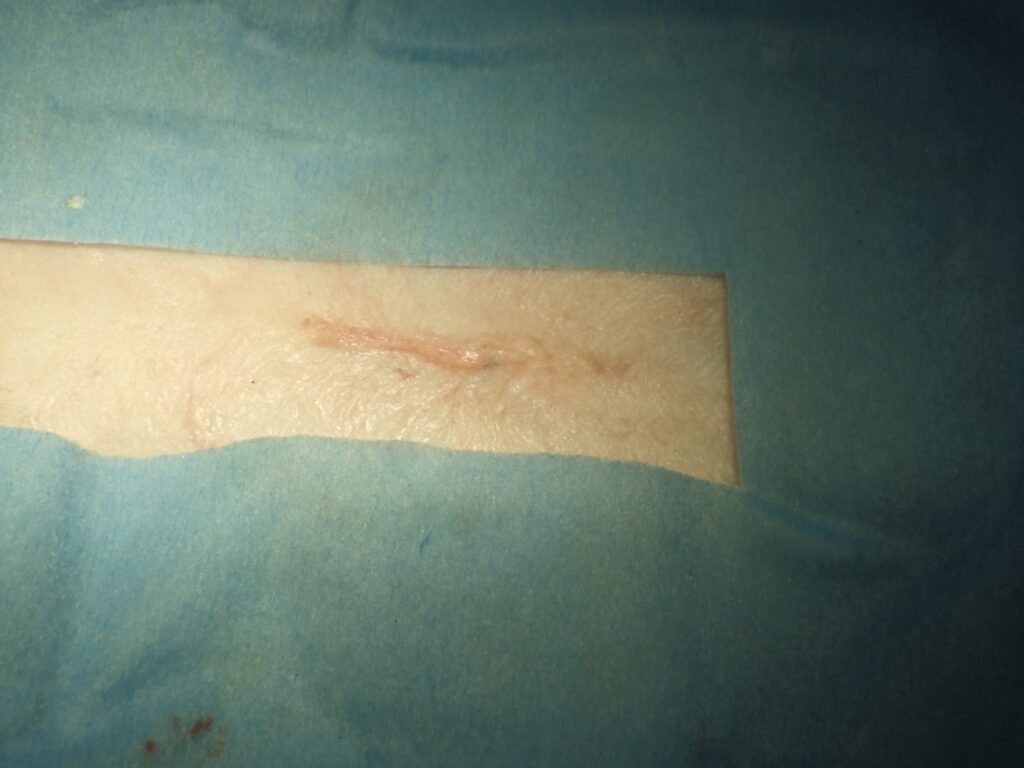

順調に行ってこんな感じです。

皮膚の外側は縫わない

皮膚の内部を縫ってテープをはるだけ

そこで当院では皮膚の中を縫った後に

フィルムを貼るという方法をとっています。

このフィルムは結構強力で、術創の違和感を軽減し治癒を早めてくれます。

これで今のところ術後にいじったウサギさんはいません。

傷跡はほぼのこりません。